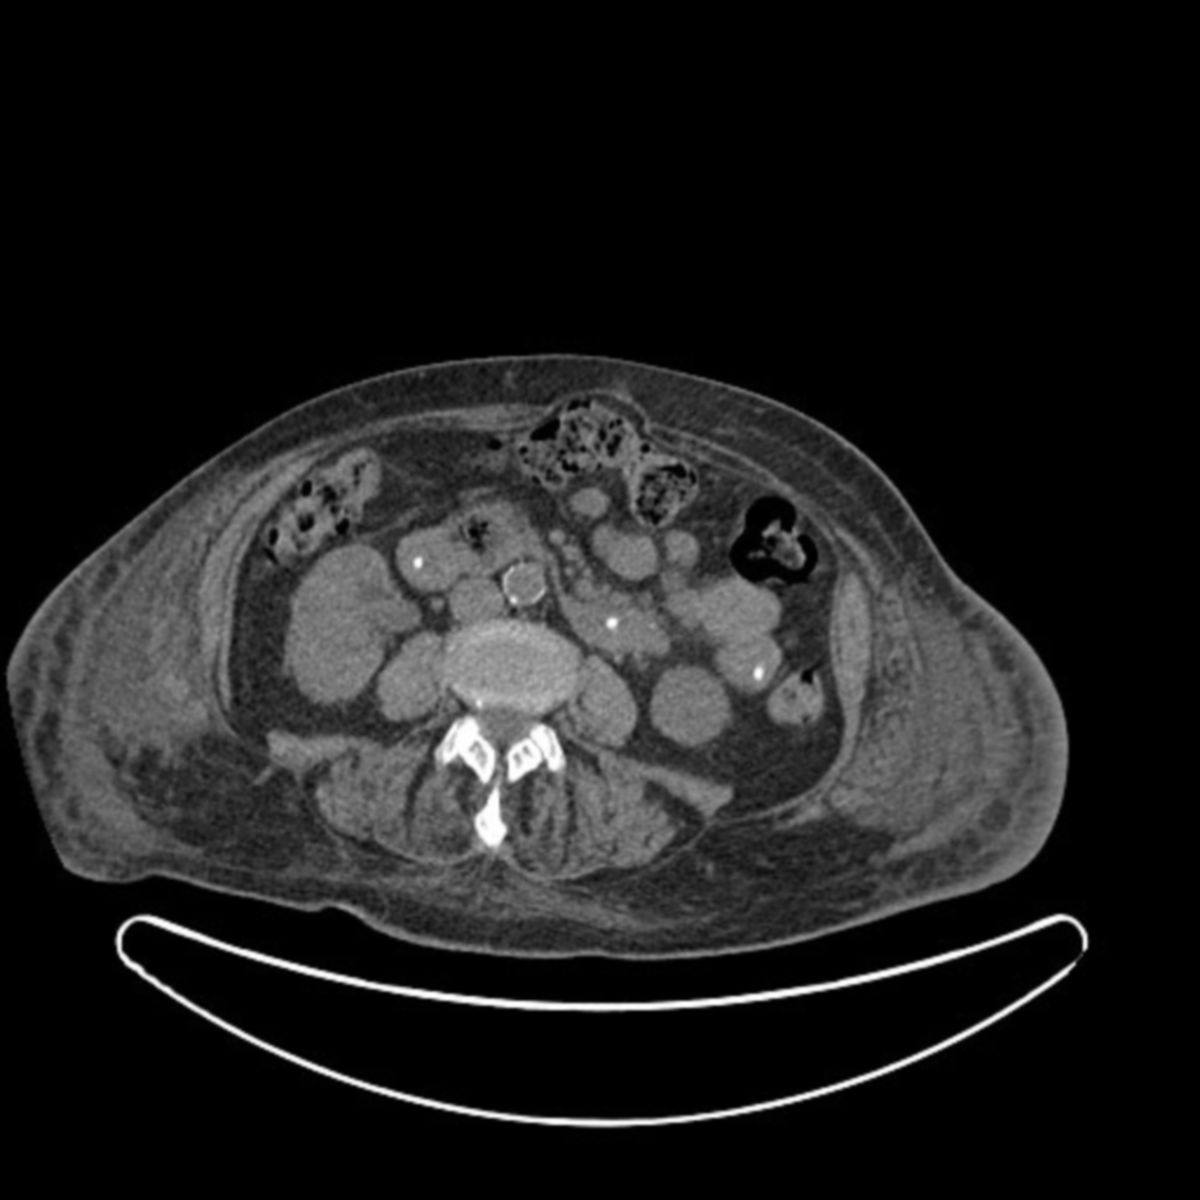

Coronal views of computed tomography scan of abdomen and pelvis with Frozen Abdomen Doccheck “it is commonly seen with. Frozen pelvis refers to a condition in which pelvic organs are distorted and tethered to each other as a consequence of adhesive processes. Rapid onset of severe abdominal symptoms potentially requiring surgical intervention. Acute abdomen refers to the rapid onset of severe symptoms of abdominal pathology. It may indicate a potentially life. Beim abdominellen kompartmentsyndrom. Frozen Abdomen Doccheck.